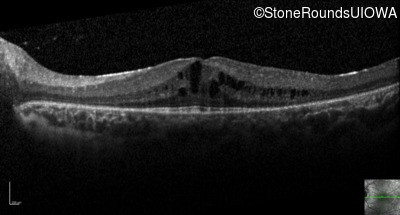

Optical Coherence Tomography - Left - 20/32

Exemplar / OCT Stack